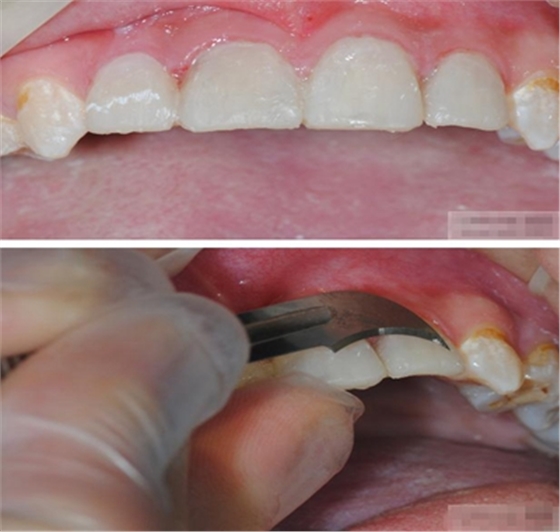

【比色】清潔牙面

比色

談到比色 要考慮天然牙:亮度 、飽和度、色相 、透明度、半透明度 ····

【基牙預(yù)備】樹(shù)脂貼面平齊牙齦邊緣是最佳設(shè)計(jì),或者使用齦上邊緣。

樹(shù)脂貼面平齊牙齦邊緣是最佳設(shè)計(jì),或者使用齦上邊緣

釉質(zhì)邊緣要用橡皮輪拋光

拋光可以去除懸釉。這樣經(jīng)過(guò)車針打磨過(guò)的釉質(zhì)表面會(huì)更加均一,形成良好的邊緣封閉。